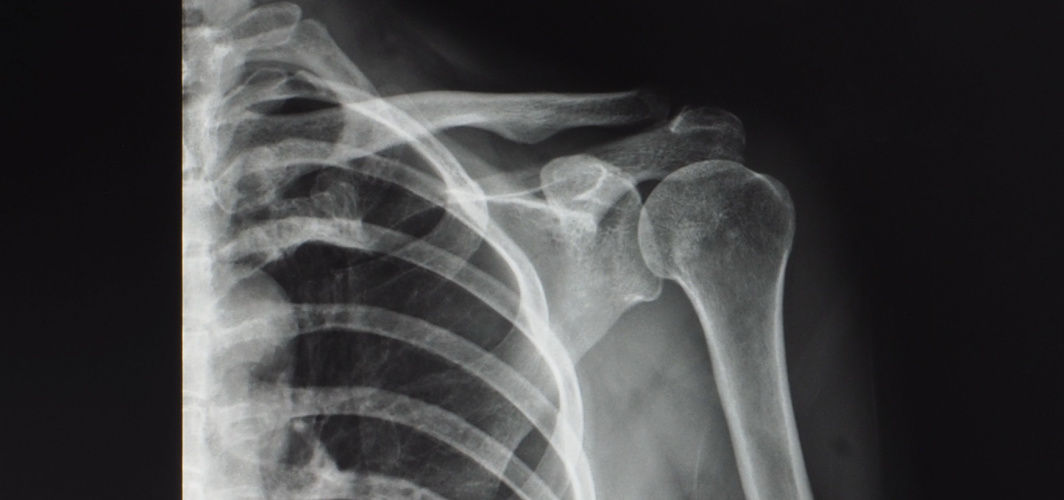

Shoulder Arthroscopy Surgery: Procedure and Recovery Time

Learn about the shoulder arthroscopy procedure, what to expect during and after surgery, and the estimated recovery time. Discover the latest advancements and factors that can contribute to a successful outcome.